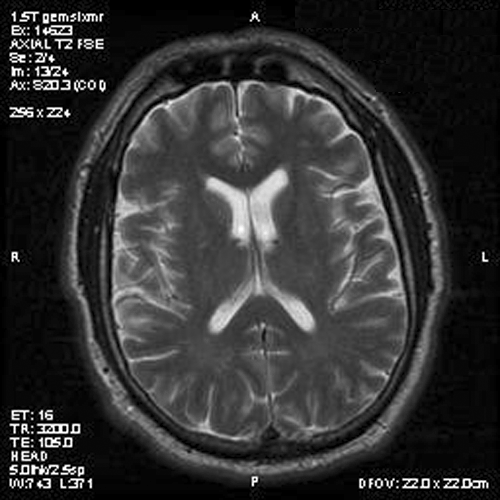

Panel A is T1-weighted post contrast MR image, Panel B is a SPGR T1-weighted post contrast MR image and Panel C is FSE T2-weighted image. Panel D and E are taken from cytologic preparation from intraoperative consultation. Panel F to H are taken from frozen sections. Panel I to L are taken from paraffin section.

Image of the case: In the left frontal horn there is a well demarcated, subependymal mass measuring approximately 1.1 x 0.5 cm which is relatively hyperintense to white matter on T1-weighted image (Panel A and B) as well as T2-weighted image (Panel C) sequences. It does not enhance on the post contrast images. There is no obstruction of the foramen of Monro.